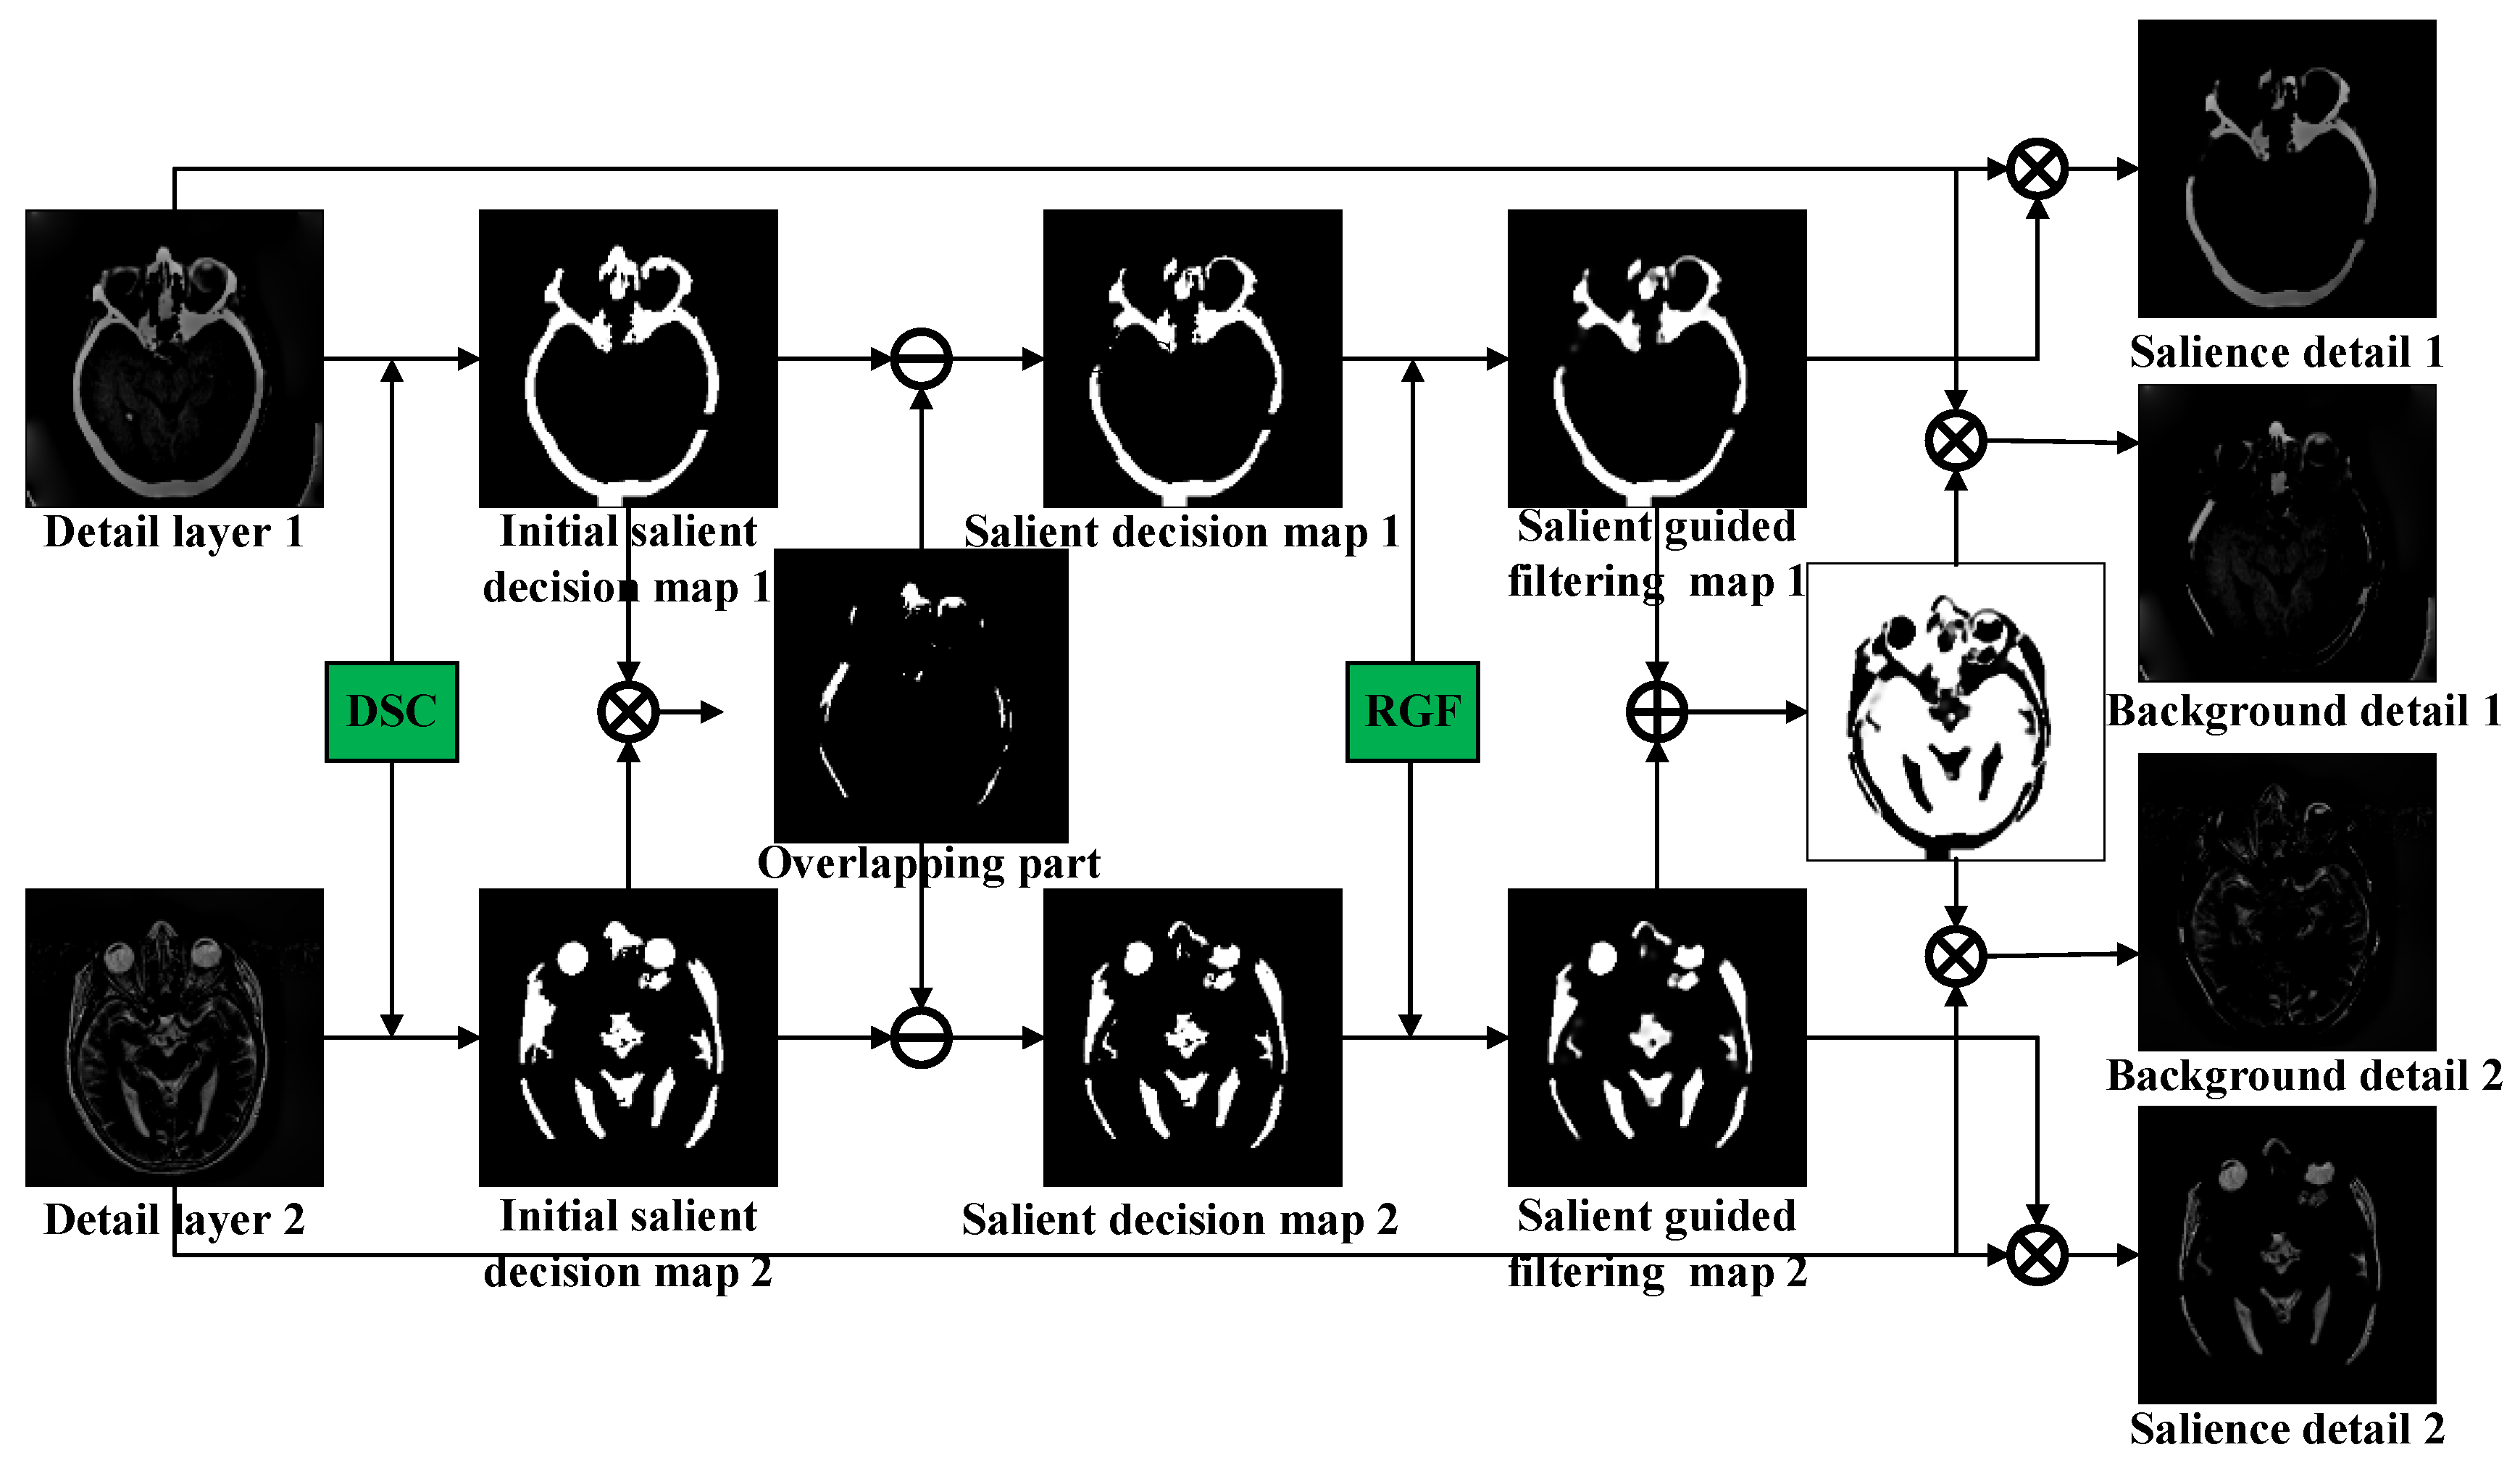

The proposed method is illustrated in Figure 1. First, the source images are decomposed into a base layer and a detail layer via the BLF-LS. The base layer, which is obtained by decomposing the source image, is fused based on the MLEN fusion rules to retain the energy information of the source image. Moreover, the detail layers are considered a superposition of the salient regions and background information. The detail layers are decomposed into background-detail layers and salient-detail layers using a model based on the DSC and RGF. To fully retain the energy information, the background-detail layer of the fused image is obtained using the fusion rule, Abs. Regarding the salient-detail layers that contain important salient targets, the overlap between the two salient-detail layers is removed using the DSC-RGF model, and a direct summation method is used to obtain the salient-detail layer of the fused image. Finally, the fused image is obtained by reconstruction.

Figure 1.

Flowchart of proposed image-fusion method.

3.2. Decomposition of Detail Layer Based on DSC-RGF Algorithm

In recent years, many saliency detection methods that can detect salient visual areas or objects and easily draw visual attention have been proposed. It is typically easier to detect salient targets in the detail layer obtained using a smoothing filter. To this end, we designed a method based on the DSC and RGF to fuse the detail layer, as shown in Figure 3; this method mainly consists of the following steps. First, the initial salient decision map is obtained by applying the DSC to the detail layer. Second, the overlapping part of the two initial salient decision maps produces ghosting in the fusion results and affects the visual effect; therefore, the overlap-removal procedure is performed on the initial salient decision map. Then, in view of the edge-smoothing problem of the significant target in the salient decision map, the RGF is used to process the salient decision map to obtain the salient guided filtering (SGF) map. Finally, the detail layer is decomposed into background and salient-detail layers using this map.

Figure 3.

Deformed smoothness constraint–rolling guidance filter (DSC-RGF) algorithm.

The details of each step are as follows. First, the DSC model is used to detect the detail layer to obtain the salient information, and threshold correction is adopted to process the salient information of the initial salient decision map.

where denotes the salient-detection operation using the DSC model in Equation (4); T is the threshold value; and and are the initial salient decision maps obtained from and , respectively.

Second, it is necessary to remove the overlapping part , which is generated by multiplying and . Directly phasing it into the fusion result causes ghosting, which affects the visual effect.

where and represent the salient decision maps obtained after removing the overlapping parts. Considering the edge-smoothing problem of the significant target in the salient decision map, we used RGF to process to obtain the SGF map.

where represents the RGF function; denotes the number of iterations; r denotes the filter size; denotes the degree of blur; and and denote the SGF maps used to decompose the detail-layer maps of the source image.

Finally, the salient-detail layers are obtained by multiplying the SGF maps by the detail layers, and the background-detail maps are obtained by removing the salient parts of the detail layers, as described below.

where and denote the salient detail layers obtained from the decomposition of and , respectively; and and denote the background detail layers obtained from the decomposition of and , respectively.